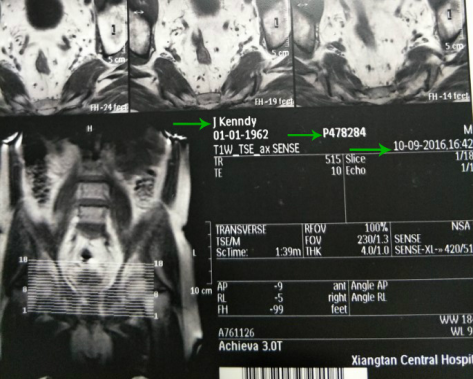

Case 1

- Mr.

John Kennedy from USA

Mr. John Kennedy had a very severe

case of prostatitis for over 14 years, which could not be killed by oral and IV

antibiotics in the USA. In 2007, John Kennedy's prostatitis was cured by 3D

Urology Clinic. Because John Kennedy received multiple prostate trans-rectal

injections in the United States in 2006, his rectal wall and prostate gland were

left a fibrous scar that could lead to prostate cancer, and anal fistula was

formed in the rectum. In recent years, blood urine has been found in the

microscope, and obvious tension and pressure feelings have appeared in the

prostate area. In 2016, his PSA test was higher than 40 ng/ml, and MRI showed

that he had prostate cancer.

1) Before receiving 3D Prostate Cancer Targeted Treatment:

The authoritative hospital’s prostate

cancer MRI check in september 2016.

He 1st MRI detected a nodule 16 X 10mm , a cancerous lesion 15 X 11 X 14mm near the center of the

prostate. (2016-9-07-before treatment).